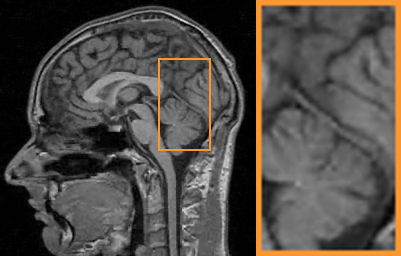

First, we test on 25 T1-weighted MRI data using three different undersampling patterns with a fixed 10% sampling rate. Fig. 3 shows the quantitative results (PSNR). Our method performances best for all three cases and has stronger stability compared with the second best method on variance. As for the effect of sampling ratios variation, we use radial mask under 10%, 30% and 50% sampling rates with evaluation of RLNE and MSE. Fig. 4 shows that our method has the lowest reconstruction error for all sampling rates. For more intuitive comparison, we illustrate the reconstruction error in term of pixels in Fig. 5. We also offer the qualitative comparison in Fig. 6. Visualized results demonstrate our method has better performance in both artifacts removing and details restoration. Time consuming is also considered. We compare our method with others on the 25 T1-weighted data using Radial mask with 10% and 50% sampling rate. Notice that ADMM-Net and ours are tested on GPU for the incorporation of deep architecture. Tab. 1 shows that our method provides an efficient reconstruction process and comes to the fastest method among the state-of-the-art competitors.

To demonstrate the robustness of our approach, we first apply it on various MRI data including the chest, cardiac and renal (?). In Tab. 2, Our proposed framework gives the highest PSNR for all of the tree types of MR images. Fig. 7 visualizes the corresponding results for chest data. we can see that our approach prevails over others in detail restoration at the junction of blood vessels as well as noise removal in the background. Actually, our method has a stronger ability to handle slight noise because of the subprocess of learning based optimization with deep prior. To demonstrate that, we add Rician noise at level of 20 to 25 T1-weighted MRI and 25 T2-weighted MRI to generate the noisy data. As what is shown in Fig. 8, our method over leads all the competitors by a large margin when the input is corrupted with Rician noise.